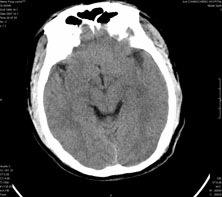

男,41岁,间断抽搐1小时,失神5分钟,bp130/90mmhg。低密度区ct值约16hu。

脑实质见多发散在的钙化点,左顶叶见一囊变灶,多考虑脑囊虫。

脑实质见多发散在的钙化点,右颞、顶叶见囊性灶,考虑脑囊虫。

多发的囊泡(多发囊型)+多发的钙化(慢性钙化型)=混合型

多发脑囊虫—混合型!活动期